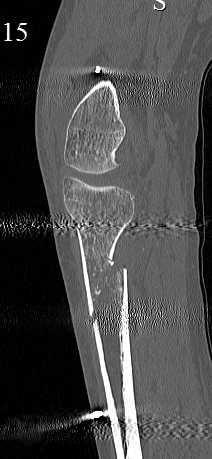

Серия КТ сканов в аппарате